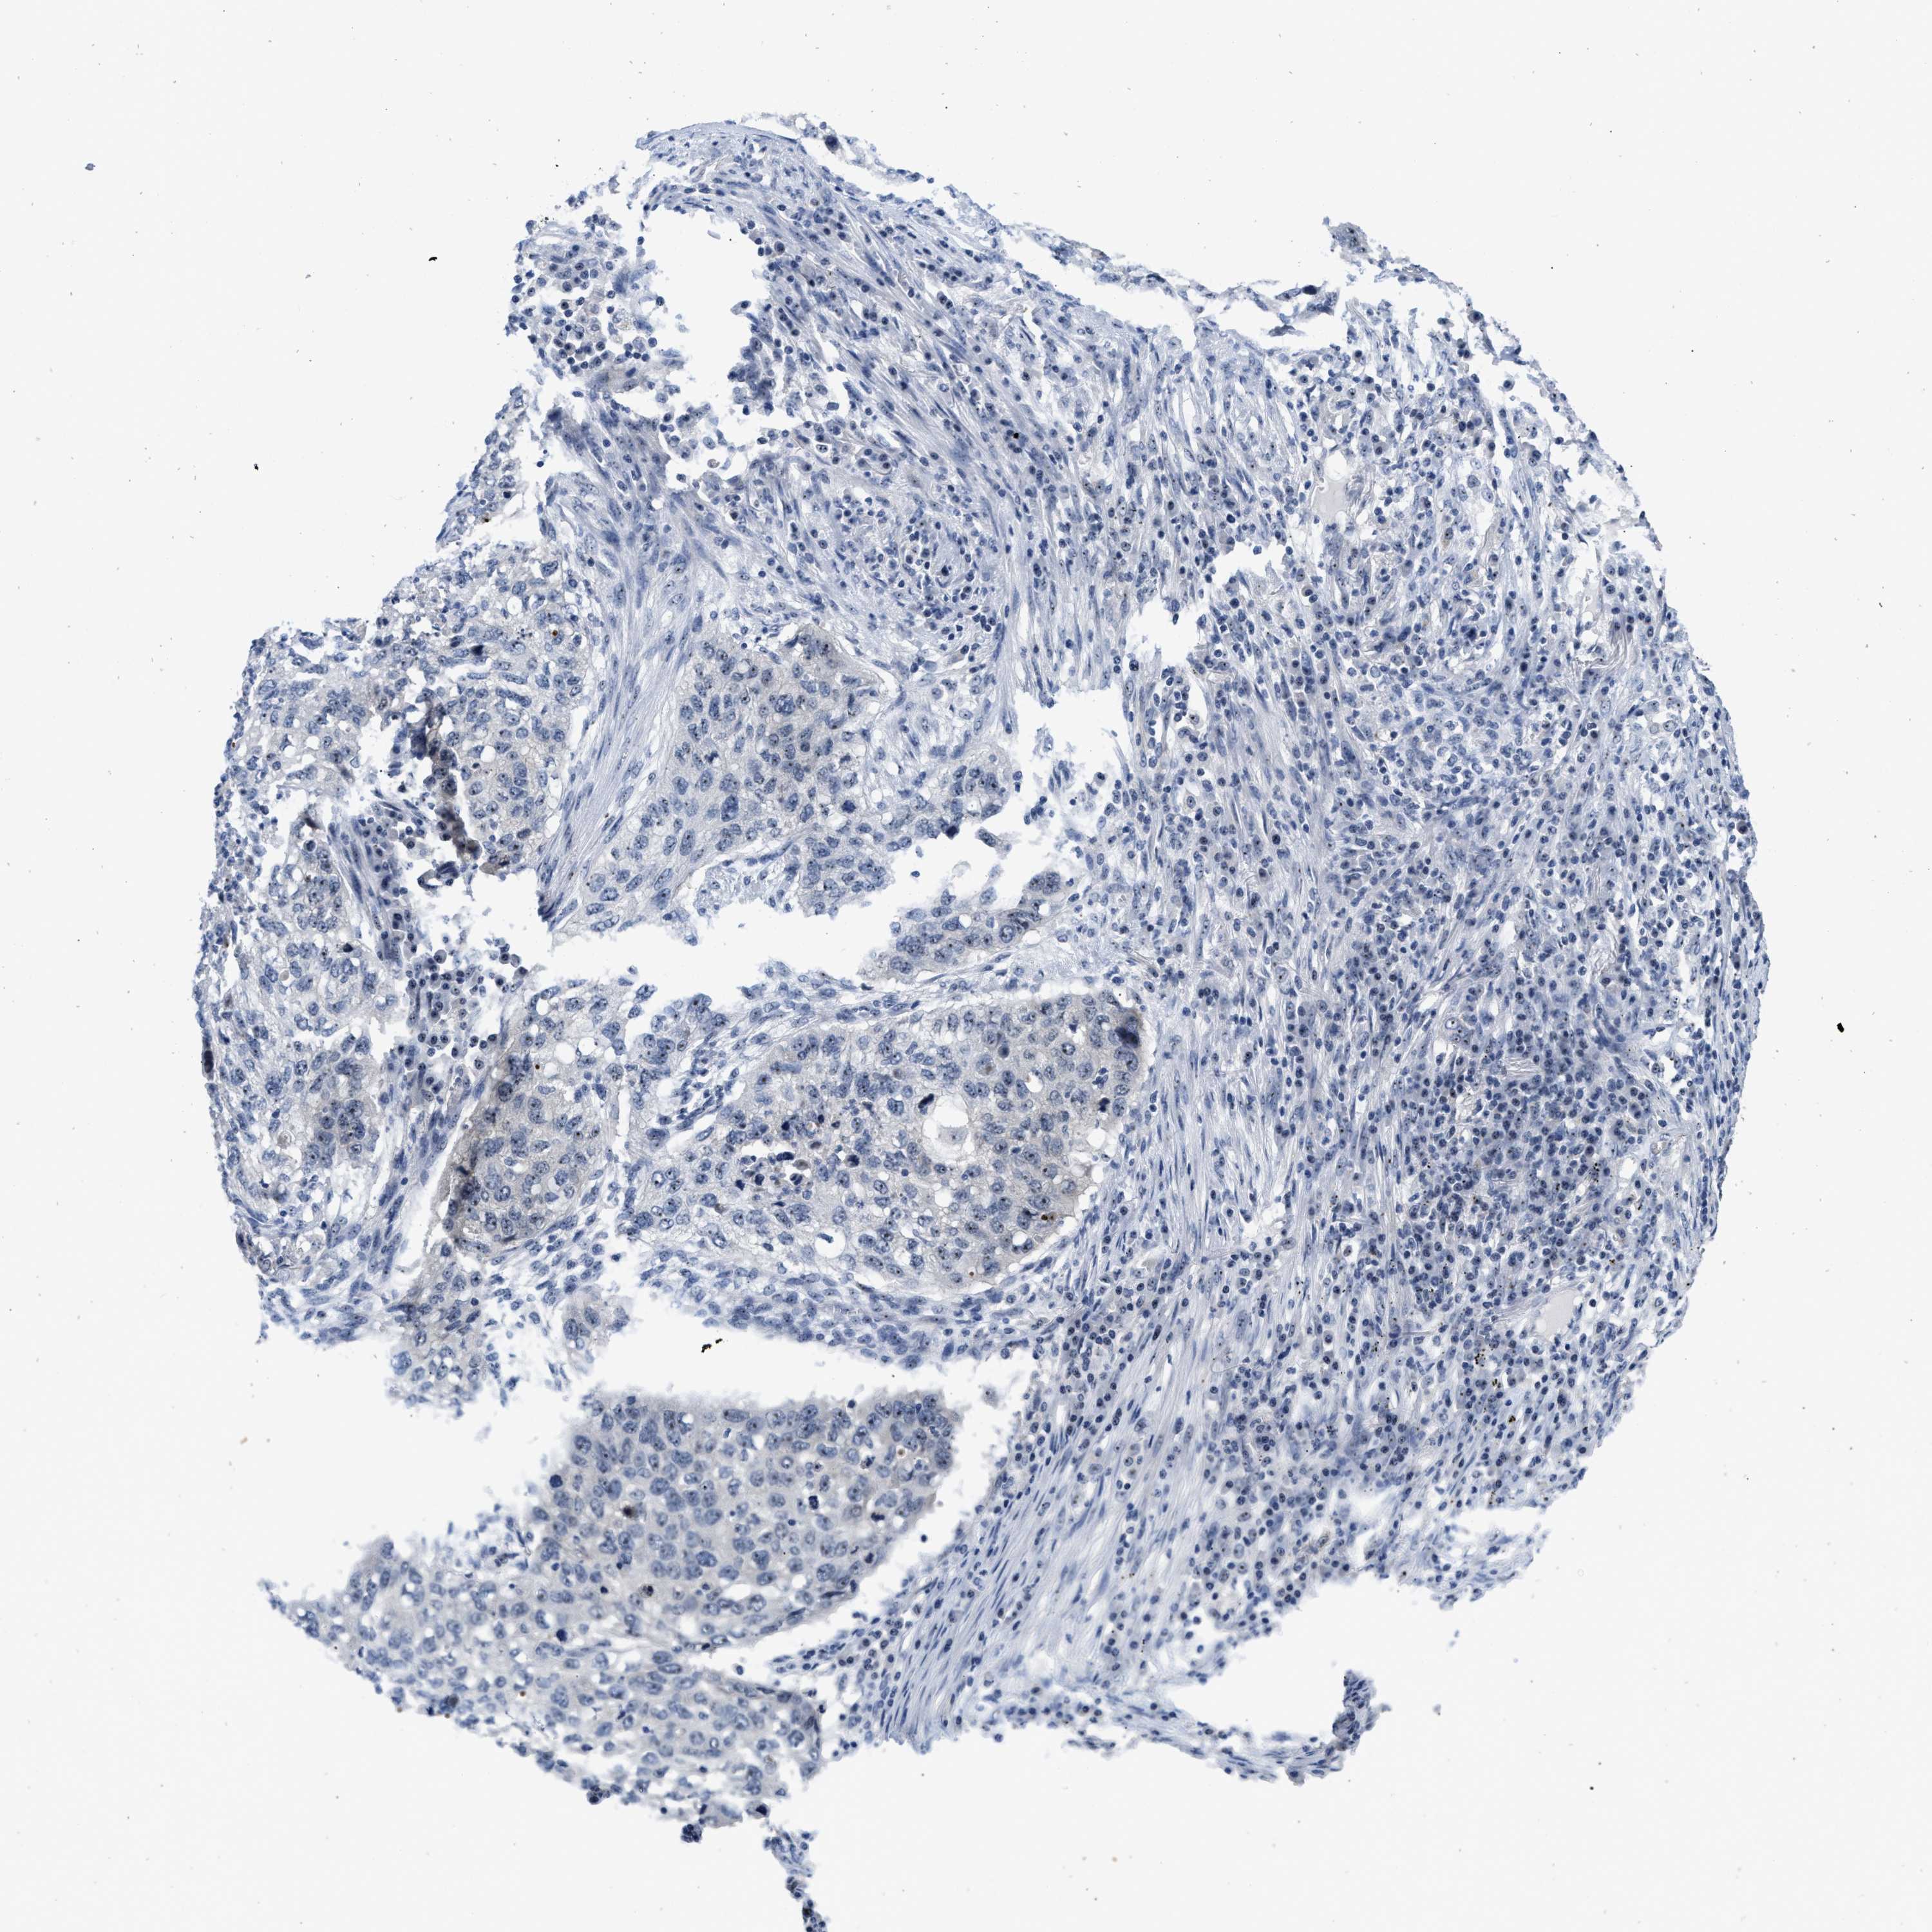

LUNG SQUAMOUS CELL CARCINOMA (TCGA) - Interactive survival scatter ploti

The Survival Scatter plot shows the clinical status (i.e. dead or alive) for all individuals in the patient cohort, based on the same data that underlies the corresponding Kaplan-Meier plots. Patients that are alive at last time for follow-up are shown in blue and patients who have died during the study are shown in red.

The x-axis shows the expression levels (FPKM) of the investigated gene in the tumor tissue at the time of diagnosis. The y-axis shows the follow-up time after diagnosis (years). Both axes are complimented with kernel density curves demonstrating the data density over the axes. The top density plot shows the expression levels (FPKM) distribution among dead (red) and alive patients (blue). The right density plot shows the data density of the survived years of dead patients with high and low expression levels respectively, stratified using the cutoff indicated by the vertical dashed line through the Survival Scatter plot. This cutoff is automatically defined based on the FPKM cutoff that minimizes the p-score. The cutoff can be changed by dragging the vertical line or by entering a cutoff value in the square labeled "Current cut-off".

Under the Survival Scatter plot the p-score landscape (black curve; left axis) is shown together with dead median separation (red curve; right axis). Dead median separation is the difference in median mRNA expression between patients who have died with high and low expression, respectively. It is calculated as follows: median FPKM expression of dead patients with high expression - median FPKM expression of dead patients with low expression. This is intended to aid the user in visually exploring custom cutoffs and the associated p-scores and dead median separation.

Individual patient data is displayed and can be filtered by clicking on one or more of the category buttons on the top of the page. Categories describing expression level and patient information include: high, low, alive, dead, female, male and tumor stages. The scale of the x-axis can be toggled between linear and log-scale by clicking on the "x log" button. Mouse-over function shows TCGA ID, patient information and mRNA expression (FPKM) for each patient.

& Survival analysisi

Kaplan-Meier plots summarize results from analysis of correlation between mRNA expression level and patient survival. Patients were divided based on level of expression into one of the two groups "low" (under cut off) or "high" (over cut off). X-axis shows time for survival (years) and y-axis shows the probability of survival, where 1.0 corresponds to 100 percent.

NOP58 is not prognostic in Lung Squamous Cell Carcinoma (TCGA)

: 47.86

P scorei

N/A

Average pTPM 65.8

Number of samples 489